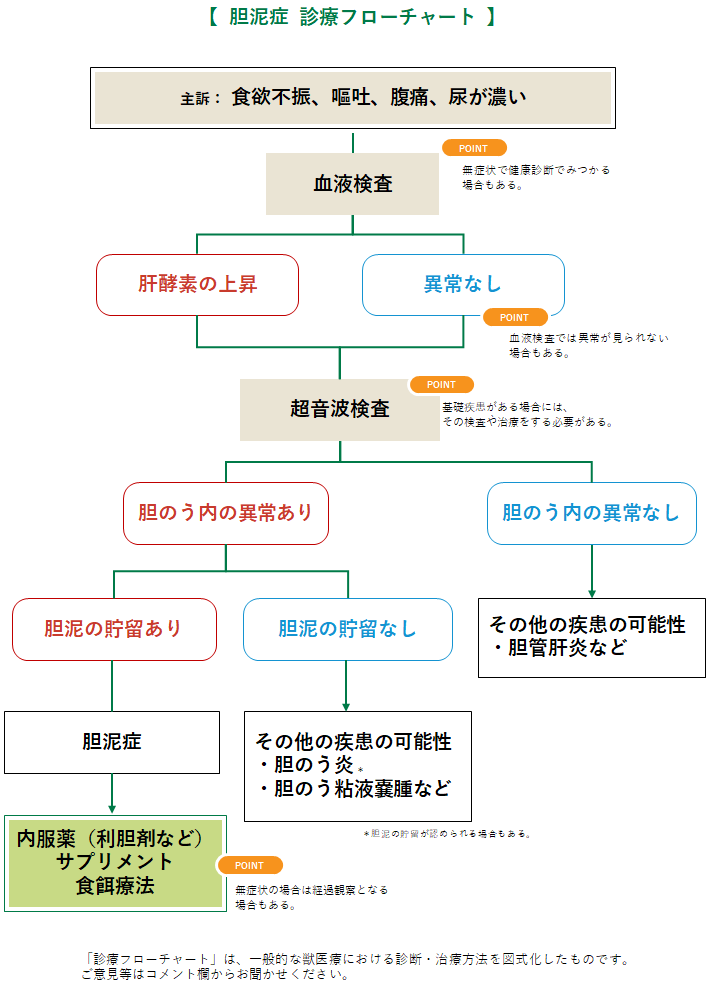

胆泥症は無症状で経過することが多いため、定期的な健康診断で早期発見を心がけましょう。 また、胆嚢炎や内分泌疾患( 甲状腺機能低下症 や 副腎皮質機能亢進症 )などのような、

犬 胆泥症 原因-胆泥 をかたちづくっているのは コレステロール や 黄疸色素 ( ビリルビン )、 カルシウム などの微細な 結晶 が 胆嚢壁 から分泌される 粘液 に包まれたものと考えられますが、他にも 炎症 によっこんにちは。獣医師の清水いと世です。 今回は、わんちゃんの胆泥症について説明します。 前編は、胆泥症の原因や検査方法や症状について、後編は治療や予防方法について説明します。 犬の胆泥

胆泥症・胆石症について 胆嚢は、胆汁を産生し貯留する器官です。 胆汁には、脂肪を分解し水に溶けやすい状態に(乳化)する役割を持っています。 胆嚢に貯えられた胆汁は、元々サラサラの水胆泥を生じさせた原因や疑われる原因があれば、それを取り除きます。 そのために、 犬の胆泥症 <前編> で説明した原因追及のための検査結果が重要になります。 肝臓の異常が認められるので